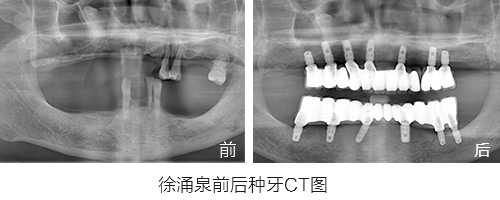

第一期种植市民“明星案例”回顾:徐涌泉

原苏州市第十七中英语老师,因为牙周炎30多岁就开始缺牙,陆陆续续共佩戴更换了5副假牙,期间多次调整,假牙带来的疼痛和牙龈发炎数不胜数。

种植情况:全口种植,即拔即种,植骨

种牙时间:2015年3月(已种牙1年5个月)

种植情况:全口种植

徐先生的种牙笔记:记录一年多的种牙经历